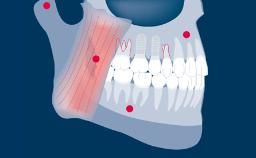

Prosthodontically driven implant planning ensures that implant placement is compatible with the desired end result, which is a key factor for successful outcomes in implant therapy.

Digital technologies now available in the field of implant dentistry facilitate prosthodontically driven implant planning. Benefits of these technologies include significant improvements in patient assessment and treatment planning, allowing clinicians to position supporting implants with a high degree of accuracy.

- discuss the indications for using computer-aided planning

- discuss limitations of computer-aided implant planning